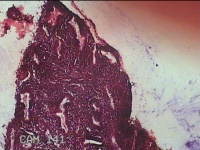

宫腔内组织

性别

女

年龄

24岁

临床诊断

稽留流产

一般病史

停经1个月余,阴道流血2天。

标本名称

大体所见

灰白暗红色不规则碎组织2x1.5x1.3cm一堆,未发现明显的绒毛样组织。